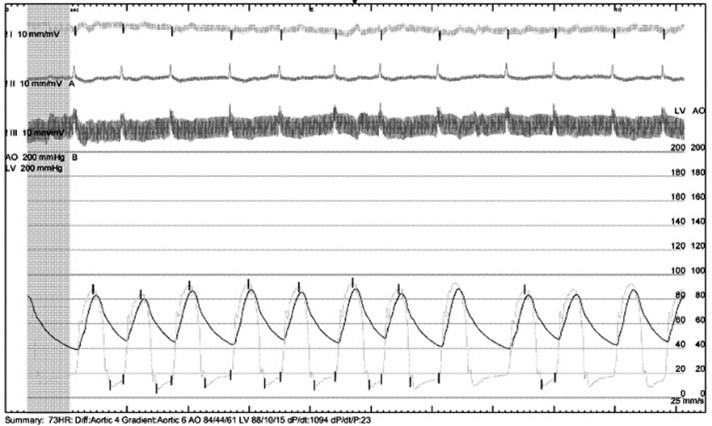

Under local anesthesia and conscious sedation, femoral arteries (FA) were accessed by 8-Fr sheath at right FA and two of 8-Fr sheaths at left FA for pigtail catheter and snare-assisted device. Aortography was conducted by pigtail catheter to locate aortic cusp. An Amplatz left catheter over a 0.035-inchJ-tip wire was placed at aortic cusp via the RFA which was then exchanged with an Amplatz Super Stiff wire to upsized 16-Fr Braidin sheath. The aortic valve was crossed with an Amplatz left catheter over a straight-tip wire under cuspoverlap views (LAO16, CAU 30), peak-to-peak gradient of 19 mmHg. During RV pacing, a Safari Extra Small guidewirewas positioned in LV and the AV was pre-dilated by an 18 × 40 mm Alwide balloon. Subsequently, a 27 mm VitaFlow valve was deployed in an optimal position under snare-assisted. Post-deployment aortography revealed mild AR, LVEDP of20 mmHg, and 4 mmHg of LVOT gradient. Post-dilation was performed by a 24 × 40mm VACC III balloon. The FA was closed by 6-Fr Proglide at the right and 8-Fr AngioSeal at the left. Post-TAVR TEE showed mild PVL without significant transvalvular gradient and preserved LVEF of 64%. One-month after the TAVR, she was diagnosed with early-stage colonic cancer. A laparoscopic hemicolectomy which completed pre-operative evaluation, coronary revascularization, TAVR and appropriated medication was performed as time-sensitive surgery following by CMT with curative intent.